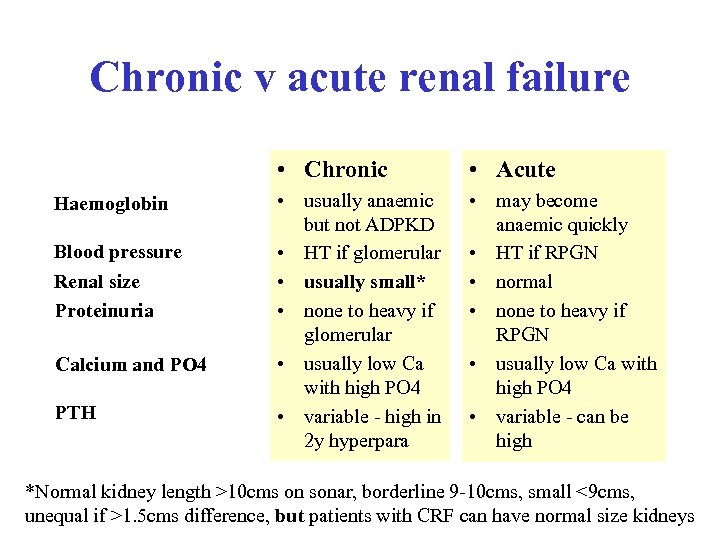

Chronic v acute renal failure • Chronic Haemoglobin Blood pressure Renal size Proteinuria Calcium and PO 4 PTH • Acute • usually anaemic but not ADPKD • HT if glomerular • usually small* • none to heavy if glomerular • usually low Ca with high PO 4 • variable - high in 2 y hyperpara • may become anaemic quickly • HT if RPGN • normal • none to heavy if RPGN • usually low Ca with high PO 4 • variable - can be high *Normal kidney length >10 cms on sonar, borderline 9 -10 cms, small <9 cms, unequal if >1. 5 cms difference, but patients with CRF can have normal size kidneys

Chronic v acute renal failure • Chronic Haemoglobin Blood pressure Renal size Proteinuria Calcium and PO 4 PTH • Acute • usually anaemic but not ADPKD • HT if glomerular • usually small* • none to heavy if glomerular • usually low Ca with high PO 4 • variable - high in 2 y hyperpara • may become anaemic quickly • HT if RPGN • normal • none to heavy if RPGN • usually low Ca with high PO 4 • variable - can be high *Normal kidney length >10 cms on sonar, borderline 9 -10 cms, small <9 cms, unequal if >1. 5 cms difference, but patients with CRF can have normal size kidneys